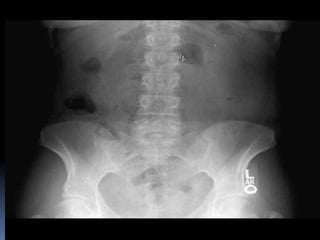

PROYECCION SIMPLE DE

ABDOMEN

CRITERIOS DE EVALUACION

P.S.A.

 Apreciar desde el

abdomen superior hasta

la sínfisis del pubis.

 Lumbares, pelvis y

ultimas costillas sin

rotación.

 Apófisis espinosas en el

centro de cuerpos

vertebrales.

 Ver el bazo, riñones,

psoas y “borde inferior

hepático

CRITERIOS DE EVALUACION P.S.A.  Apreciar desde el abdomen superior hasta la sínfisis del pubis.  Lumbares, pelvis y ultimas costillas sin rotación.  Apófisis espinosas en el centro de cuerpos vertebrales.  Ver el bazo, riñones, psoas y “borde inferior hepático

INTERPRETACION  Estructuras óseas (densidades).  Tejido blando  Psoas.  Bazo  Niveles Hidroareos.  I.D.  Colon  Silueta Renal